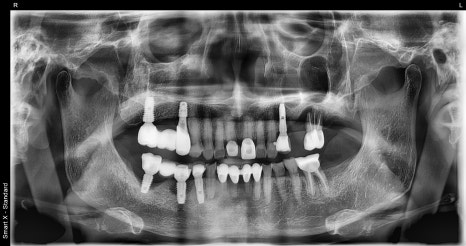

First photo: Panoramic X-ray after treatment completion. The newly placed #15 implant was connected with the existing #17 implant to restore molar function.

Second photo: Intraoral view after treatment.

The front tooth crowns and molar implant prosthetics were completed, resulting in a proper bite and greatly reduced discomfort while eating.

The implants integrated stably, and two months later the prosthetic work for the upper right premolar implant was also completed.